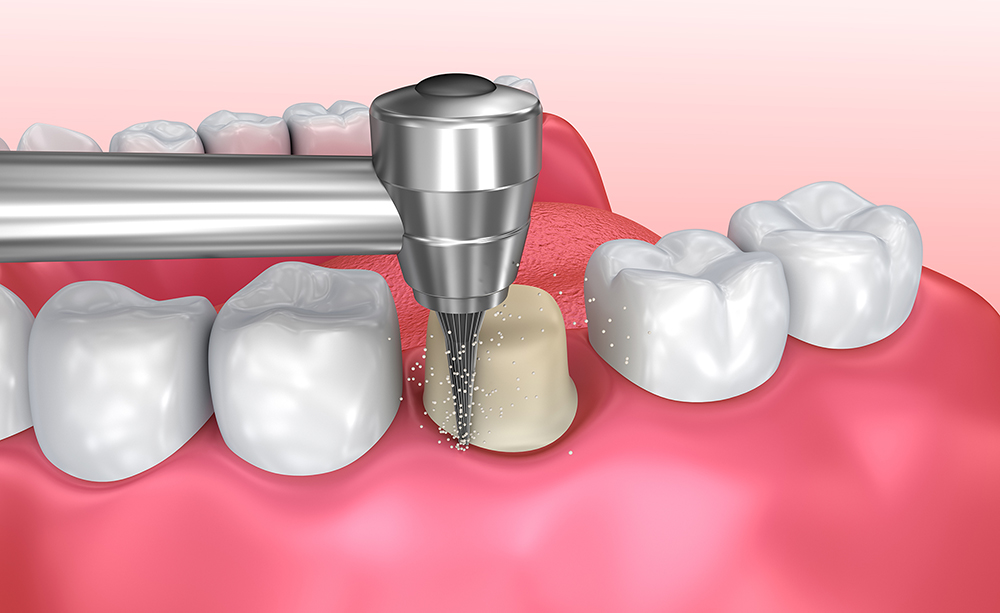

Preparación del diente

Prótesis fija dento-soportada

Este tipo de rehabilitación tiene como finalidad la reposición de las ausencias dentarias utilizando los dientes del paciente como punto de anclaje fijo para la futura prótesis. Para tal fin, será necesario llevar a cabo la correcta preparación de los dientes que servirán de pilar mediante un tallado que varía en función de la forma y el tamaño del diente. Si bien es cierto que en ocasiones los pacientes refieren tras el tratamiento cierto grado de sensibilidad frente a determinados estímulos, como los cambios de temperatura. Cuando tales molestias persisten en el tiempo, puede ser necesaria la realización de una endodoncia. Rehabilitaciones complejas por medio de una prótesis fija dento-soportada pueden requerir un período de adaptación en el que el paciente podrá percibir una mayor cantidad de salivación e incluso llegar a morderse la lengua o las mejillas. Como en cualquier tratamiento odontológico, resulta indispensable acudir periódicamente a las correspondientes revisiones para poder determinar posibles problemas, como movimiento de la/-s corona/-s por descementado de la/-s misma/-s o fracturas de la cerámica como consecuencia de fuerzas masticatorias intensas, entre otros.